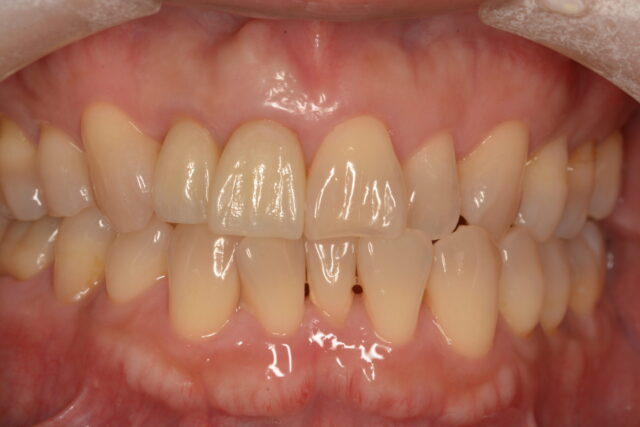

審美歯科治療 AESTHE当院では、「日本補綴歯科学会」専門医の資格を持つ院長が、セラミックスなどの白い詰め物や被せ物の審美歯科治療を行います。

セラミックスという材質のメリットは、見た目が自然だという点だけでなく、最大の特徴として、汚れが付きにくく落としやすいという優れた性質があります。そのため治療した歯が再び虫歯になってしまう「二次虫歯」のリスクも抑えられます。

ただし、そのセラミックスの材質を生かすためには、様々な工夫や、テクニックを必要とします。 -